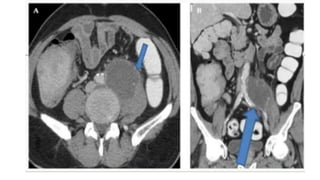

● Computed tomography (CT) is the optimal radiographic modality to evaluate for

psoas abscess though sensitivity may be limited early in the course of disease.

 In most cases, an abscess is obvious; other findings may include a focal

hypodense lesion, infiltration of surrounding fat, and gas or an air fluid level

within the muscle.

 Low density mass in retroperitoneum

 Is the modality of choice/ Gold standard

Imaging ● Computed tomography(CT) is the optimal radiographic modality to evaluate for psoas abscess though sensitivity may be limited early in the course of disease.  In most cases, an abscess is obvious; other findings may include a focal hypodense lesion, infiltration of surrounding fat, and gas or an air fluid level within the muscle.  Low density mass in retroperitoneum  Is the modality of choice/ Gold standard